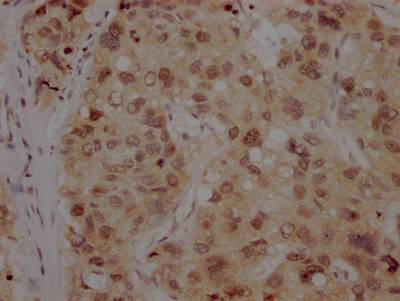

IHC image of CSB-RA916472A0HU diluted at 1:100 and staining in paraffin-embedded human lung cancer performed on a Leica BondTM system. After dewaxing and hydration, antigen retrieval was mediated by high pressure in a citrate buffer (pH 6.0). Section was blocked with 10% normal goat serum 30min at RT. Then primary antibody (1% BSA) was incubated at 4℃ overnight. The primary is detected by a Goat anti-rabbit IgG polymer labeled by HRP and visualized using 0.05% DAB.